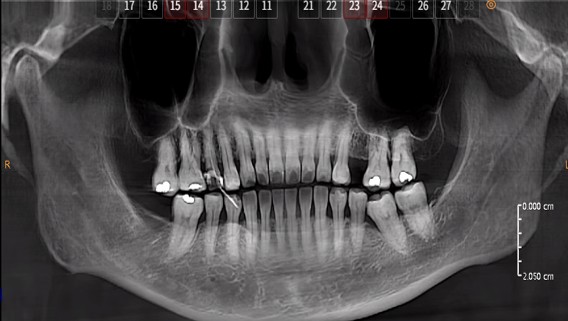

After endodontic treatment (root canal treatment), crown restoration is an in complete treatment, not an optional one:

1.Small defect: Resin filling is applicable;

2.Large defect/functional teeth (e.g., mandibular first molars, the main occlusal teeth): Crown or onlay restoration is mandatory;

1. Loss of hard tooth tissue due to caries and cavity preparation during treatment, decreased water content, and reduced fracture resistance;

4. Lack of restorative protection easily leads to reinfection of the root canal.